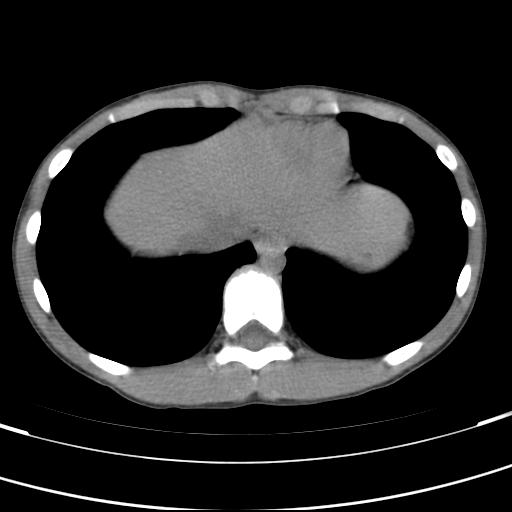

标题: PED3157:左肾缺如,请教脾脏的改变?、、

男孩,9岁。胃部不适。

脾脏位于左侧,但数个脾脏呈分离状态,左肾缺如,右肾代偿肥大。考虑多脾综合征。